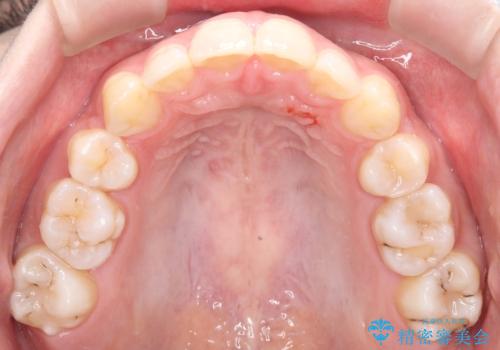

重度の歯のがたつきを、目立たない矯正と抜歯で根本改善

- 前歯から奥歯にかけて歯の重なりが激しい歯のがたつき(重度叢生)を主訴にご来院されました。精密検査の結果、歯が並ぶスペースが大幅に不足しており、歯並びを整え、口元を美しく引っ込めるためには、スペースの確保が必要と診断しました。そこで、上下左右の第一小臼歯(4番目の歯)を計4本抜歯し、そのスペースを利用して歯並び全体を整える抜歯矯正の治療計画を立案。装置には、透明で目立たないインビザラインを採用し、審美性と治療効果の両立を目指しました。

今回の治療では、重度の叢生を改善するため、まず計画通り上下左右4本の小臼歯を抜歯し、歯を並べるための十分なスペースを確保しました。装置には透明で取り外し可能なインビザラインを使用。抜歯によってできたスペースを最大限に活用し、マウスピースを定期的に交換しながら、デコボコを解消しつつ、前歯を効果的に後退させました。

治療の結果、長年の悩みであった重度の歯のがたつきが解消され、口元の突出感も改善。機能的にも安定し、審美的にも美しい、理想的な歯並びを獲得していただけました。